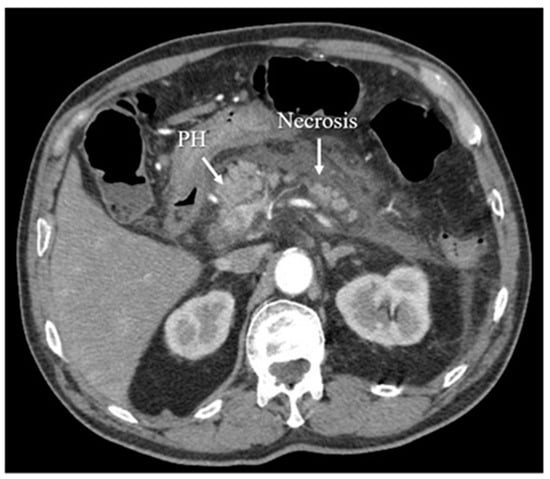

3.5. Computed Tomography

- Raghuwanshi, S.; Gupta, R.; Vyas, M.M.; Sharma, R. CT evaluation of acute pancreatitis and its prognostic correlation with CT severity index. J. Clin. Diagn. Res. 2016, 10, TC06. [Google Scholar] [CrossRef]

- Balthazar, E.J. Acute pancreatitis: Assessment of severity with clinical and CT evaluation. Radiology 2002, 223, 603–613. [Google Scholar] [CrossRef]

- Balthazar, E.J.; Robinson, D.L.; Megibow, A.J.; Ranson, J.H.C. Acute pancreatitis: Value of CT in establishing prognosis. Radiology 1990, 174, 331–336. [Google Scholar] [CrossRef]

- Mortelé, K.J.; Mergo, P.J.; Taylor, H.M.; Wiesner, W.; Cantisani, V.; Ernst, M.D.; Kalantari, B.N.; Ros, P.R. Peripancreatic vascular abnormalities complicating acute pancreatitis: Contrast-enhanced helical CT findings. Eur. J. Radiol. 2004, 52, 67–72. [Google Scholar] [CrossRef]